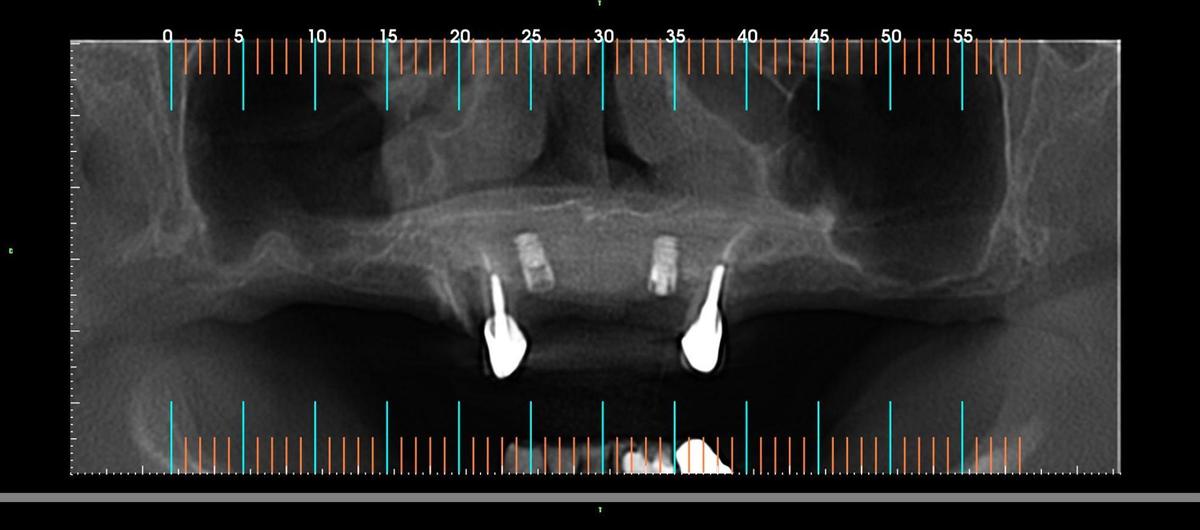

PRÓTESE TOTAL FIXA EM IMPLANTES

J.L.E.B.